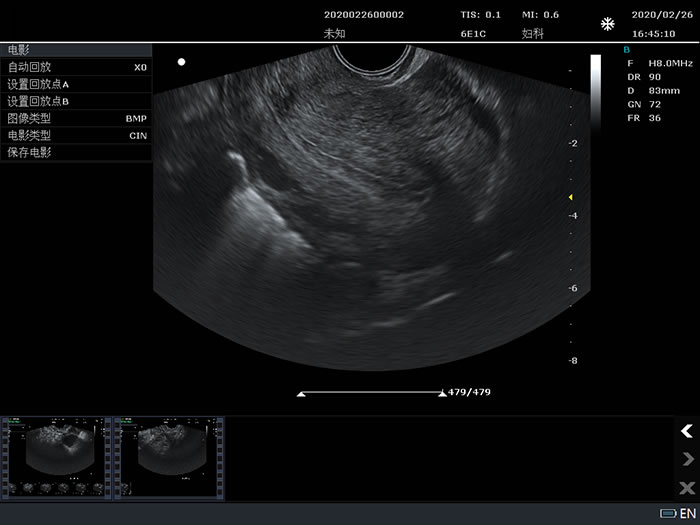

6E1C: 6.5MHz/R10/128,EndocavityConvex array probe;

6E1C: 6.5MHz/R10/128,EndocavityConvex array probe for Visual abortion;

Gynecology

6E1C: 6.5MHz/R10/128,EndocavityConvex array probe;

6E1C: 6.5MHz/R10/128,EndocavityConvex array probe for Visual abortion;

Gynecology